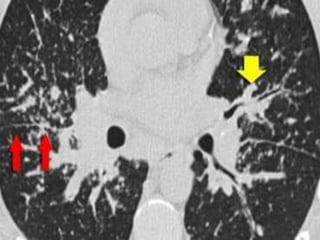

HRCT findings in Sarcoidosis.

• Common findings:

– Small nodules in a perilymphatic distribution

(i.e. along subpleural surface and fissures, along

interlobular septa and the peribronchovascular

bundle).

– Upper and middle zone predominance.

– Lymphadenopathy in left hilus, right hilus and

paratracheal (1-2-3 sign). Often with

calcifications.

SARCOIDOSIS: typical presentation

Uncommon findings:

– Conglomerate masses in a perihilar location.

– Larger nodules (> 1cm in diameter, in < 20%)

– Grouped nodules or coalescent nodules

surrounded by multiple satellite nodules (sarcoid

galaxy sign)

• Nodules so small and dense that they appear as

ground glass or even as consolidations (alveolar

sarcoidosis)

• Reverse halo sign